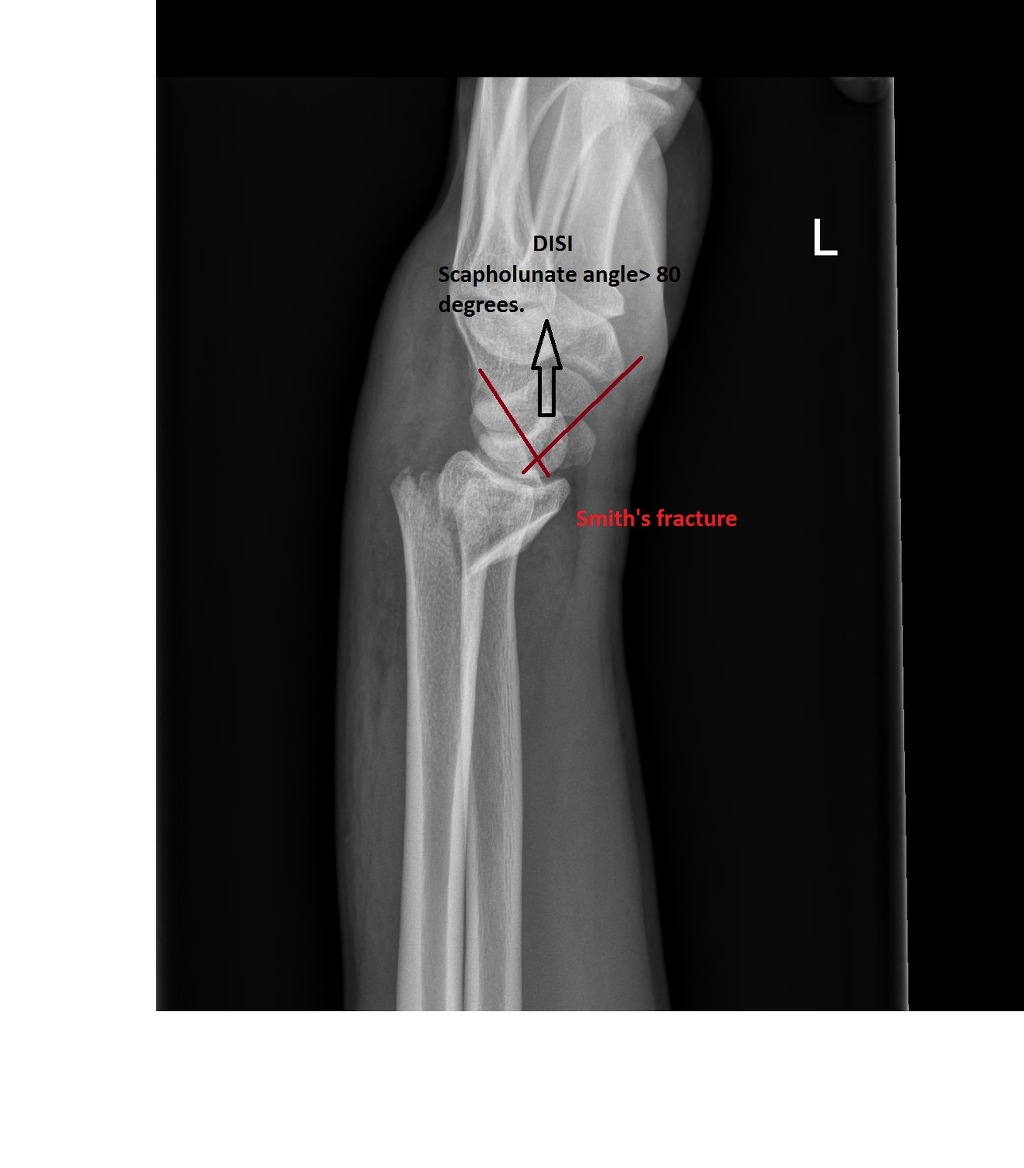

17. 손등 사이 분절 불안정성(DISI)과 손바닥 사이 분절 불안정성(VISI)에 대해 정의하라.

DISI와 VISI는 손목의 측면 방사선 사진 상에서 월상골의 기울임에 의한 수근골의 불안정성을 의미한다. DISI는 월상골이 손등 방향으로 기울어져 있는 것을 말하며, VISI는 월상골이 손바닥 방향으로 기울어져 있는 것을 말한다.

△ A 그림은 DISI(Dorsal intercalated segmental instability)

B 그림은 VISI(Volar intercalated segmental instability)

DISI (이미지 출처 : http://www.emergucate.com/)

18. 다음 골절에 해당하는 방사선 영상은?

Smith